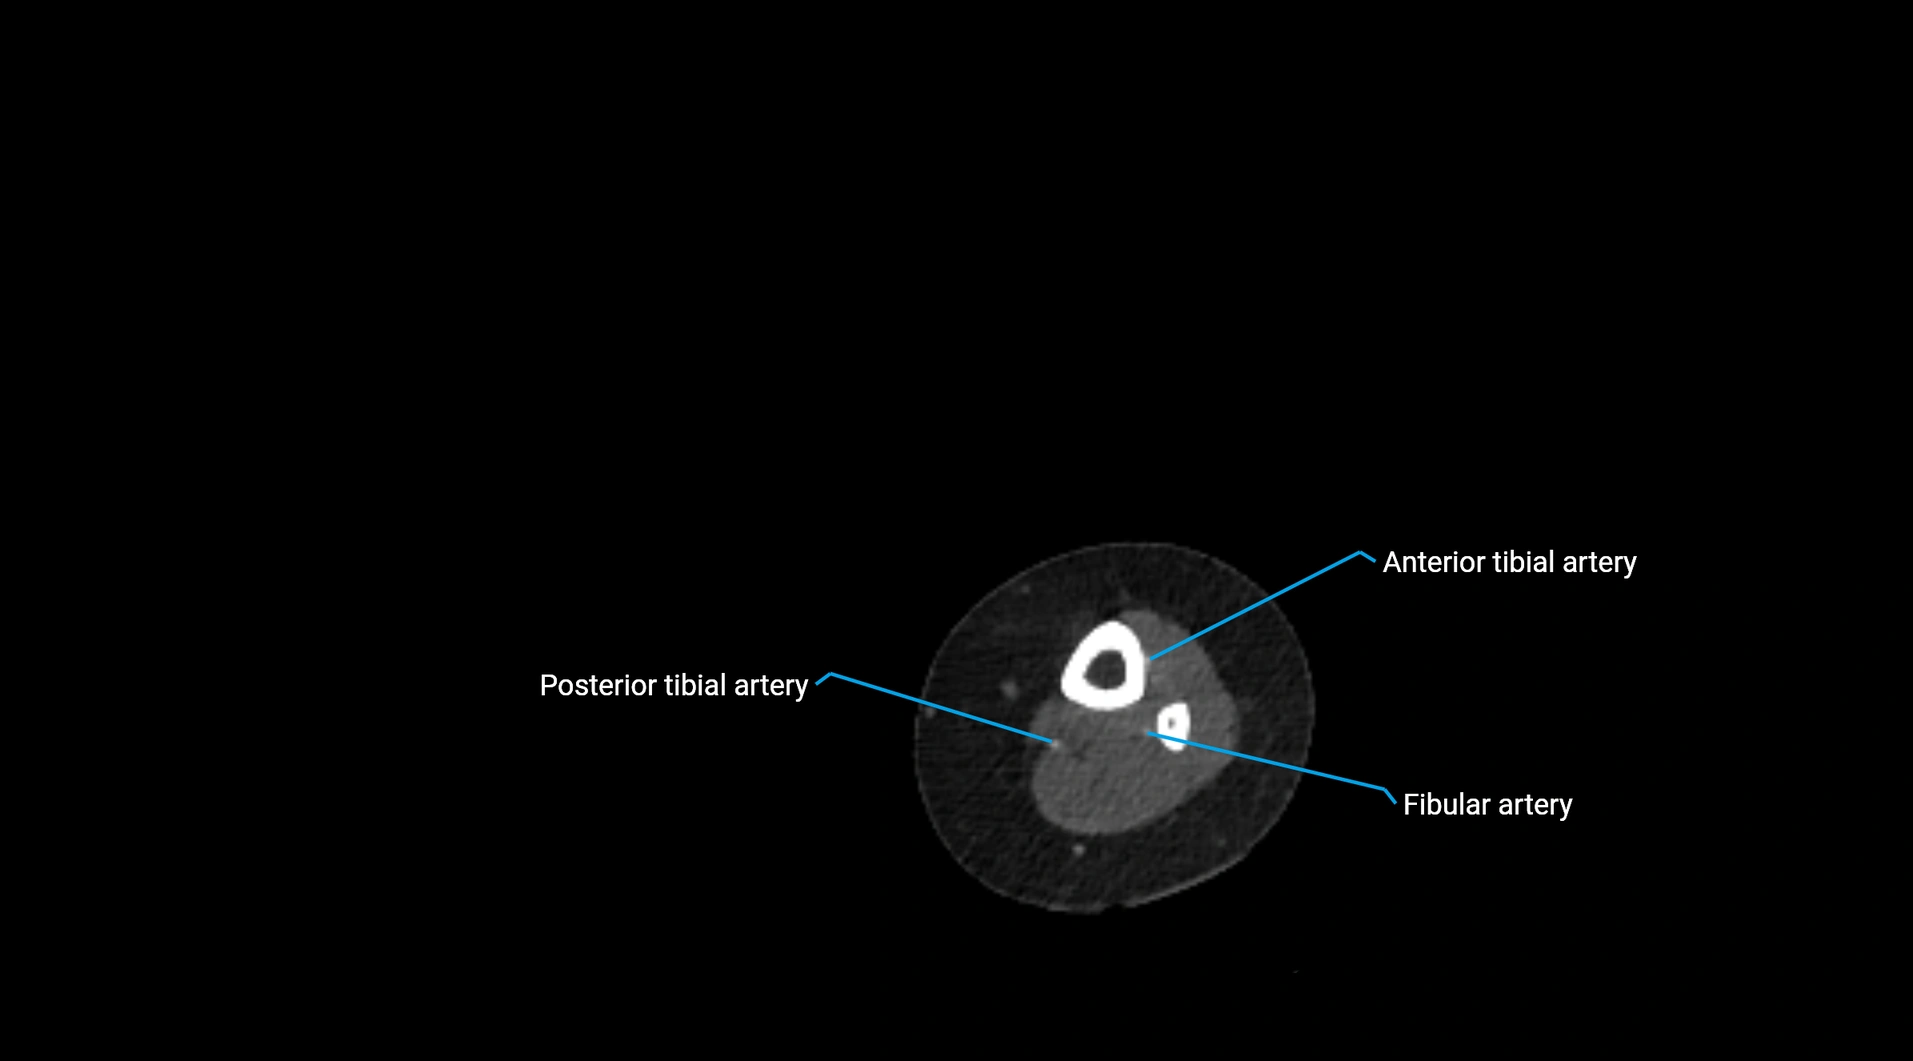

CT images

image

Contrast-enhanced CT (CTA):

• Gold standard for abdominal aortic imaging

• Provides excellent detail of lumen, wall, aneurysm, thrombus, and branch vessels

• Multiplanar and 3D reconstructions help in aneurysm measurement, stent graft planning, and dissection evaluation